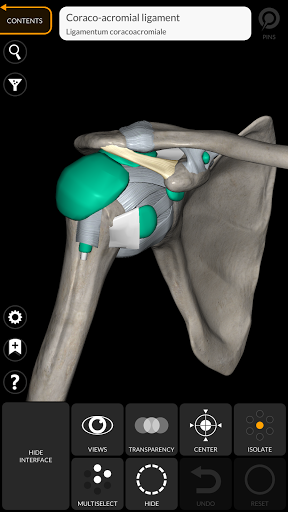

"Anatomy 3D Atlas" memungkinkan Anda mempelajari anatomi manusia dengan cara yang mudah dan interaktif.

Melalui antarmuka yang sederhana dan intuitif, Anda dapat mengamati setiap struktur anatomi dari sudut mana pun.

Model 3D anatomi sangat terperinci dan memiliki tekstur hingga resolusi 4k.

saraf • Sistem pernapasan • Sistem pencernaan • Sistem urogenital (pria dan wanita) • Sistem endokrin • Sistem limfatik • Sistem mata dan telinga FITUR • Antarmuka yang sederhana dan intuitif • Putar dan perbesar setiap model dalam ruang 3D • Opsi untuk menyembunyikan atau mengisolasi satu atau beberapa model yang dipilih • Filter untuk menyembunyikan atau menampilkan setiap sistem • Fungsi pencarian untuk menemukan setiap bagian anatomi dengan mudah • Fungsi penanda untuk menyimpan tampilan khusus • Rotasi cerdas yang menggerakkan pusat rotasi secara otomatis • Fungsi transparansi • Visualisasi otot melalui tingkat lapisan dari yang superfisial hingga yang terdalam • Dengan memilih model atau pin, istilah anatomi terkait akan muncul • Deskripsi otot: asal, • Tampilkan/ Sembunyikan antarmuka UI (sangat berguna dengan layar kecil) MULTIBAHASA • Istilah anatomi dan antarmuka pengguna tersedia dalam 11 bahasa: Latin, Inggris, Prancis, Jerman, Italia, Portugis, Turki, Rusia, Spanyol, Mandarin, Jepang, dan Korea • Istilah anatomi dapat ditampilkan dalam dua bahasa secara bersamaan PERSYARATAN SISTEM • Android 8.0 atau yang lebih baru, perangkat dengan RAM minimal 3GB Reversi

Ligamen ditambahkan